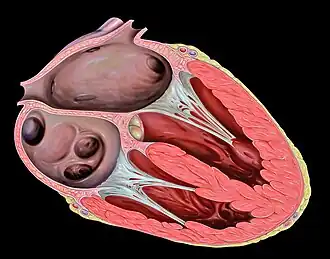

O coração humano divide-se em quatro cavidades. Na parte superior situam-se as aurículas direita e esquerda e, na parte inferior, os ventrículos direito e esquerdo.[4][5] É comum designar o conjunto da aurícula e do ventrículo direitos por "coração direito" e o conjunto equivalente do lado esquerdo por "coração esquerdo".[6] Num coração saudável, as válvulas cardíacas fazem com que o sangue dentro do coração flua em sentido único, impedindo o seu refluxo.[3] O coração é envolvido pelo pericárdio, uma membrana protetora em forma de saco que contém uma pequena quantidade de líquido. A parede do coração é constituída por três camadas: o epicárdio, o miocárdio e o endocárdio.[7] O coração dos restantes mamíferos e das aves apresenta igualmente quatro cavidades.[4] O coração dos peixes apresenta apenas duas cavidades, uma aurícula e um ventrículo, enquanto o dos répteis apresenta três cavidades.[5]

Cavidades

O coração humano possui quatro cavidades, ou câmaras: duas aurículas na parte superior e dois ventrículos na parte inferior. As aurículas recebem o sangue, enquanto os ventrículos têm a função de o bombear. O conjunto da aurícula e ventrículo direitos denomina-se "coração direito" e, da mesma forma, o conjunto da aurícula e ventrículo esquerdos denomina-se "coração esquerdo".[6]

As aurículas estão separadas dos ventrículos pelas válvulas auriculoventriculares presentes no septo atrioventricular. Os ventrículos estão separados entre si pelo septo interventricular,[19] enquanto as duas aurículas estão separadas entre si pelo septo interauricular. O septo interventricular é muito mais espesso que o septo interauricular, uma vez que durante a contração os ventrículos geram uma pressão muito superior.[7] A separação das cavidades pode também ser observada por sulcos presentes na superfície externa do coração. O sulco coronário separa as aurículas dos ventrículos, enquanto os sulcos interventriculares anterior e posterior separam os ventrículos.[19]

Coração direito

O coração direito é constituído por duas cavidades, a aurícula direita e o ventrículo direito, separados pela válvula tricúspide.[7] A aurícula direita recebe sangue de forma quase contínua a partir das duas principais veias do corpo, a veia cava superior e inferior. A aurícula direita recebe ainda uma pequena quantidade de sangue da circulação coronária através do seio coronário, situado imediatamente acima da abertura da veia cava inferior.[7] Na parede da aurícula situa-se também uma depressão denominada fossa oval, a qual é um vestígio de uma abertura durante o desenvolvimento fetal denominada forame oval.[7] A maior parte da superfície interna da aurícula direita é lisa, embora a fossa oval seja rugosa e a superfície anterior possua cristas de músculo pectíneo.[7]

A aurícula direita encontra-se ligada ao ventrículo direito pela válvula tricúspide.[7] As paredes do ventrículo direito encontram-se revestidas com trabéculas cárneas, colunas de músculo cardíaco revestidas por endocárdio. Para além destas colunas, as paredes são também reforçadas por uma banda de músculo cardíaco denominada trabécula septomarginal, a qual é também fundamental para a condução dos impulsos elétricos cardíacos. Esta estrutura tem origem na parte inferior do septo interventricular e atravessa o espaço interior do ventrículo direito para se ligar ao músculo papilar inferior.[7] Quando se contrai, o ventrículo direito bombeia o sangue para o tronco da artéria pulmonar. A passagem do sangue entre o coração direito e o tronco pulmonar é controlada pela válvula pulmonar. O tronco divide-se então nas artérias pulmonares direita e esquerda, que transportam o sangue pobre em oxigénio para cada um dos pulmões.[7]

Coração esquerdo

O coração esquerdo possui duas cavidades: a aurícula esquerda e o ventrículo esquerdo, separados pela válvula mitral.[7] A aurícula esquerda recebe o sangue oxigenado que regressa dos pulmões através de uma das quatro veias pulmonares. Tal como a aurícula direita, a aurícula esquerda é revestida por músculo pectíneo.[22] A aurícula esquerda encontra-se ligada ao ventrículo esquerdo pela válvula mitral.[7] O ventrículo esquerdo é muito mais espesso em comparação com o direito, uma vez que exerce uma força muito superior para bombear o sangue para todo o corpo. Tal como o ventrículo direito, também apresenta trabéculas cárneas, mas não possui trabécula septomarginal. O ventrículo esquerdo bombeia o sangue para o corpo através da válvula aórtica para a artéria aorta. Por cima da válvula aórtica encontram-se dois pequenos orifícios que transportam sangue para o próprio coração, através da artéria coronária esquerda e direita.[7]